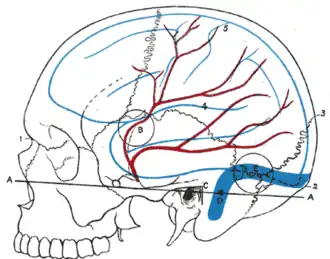

El cerebro, la arteria meníngea media y la superficie del cráneo humano. (El hueso nasión aparece con el número 1). | ||